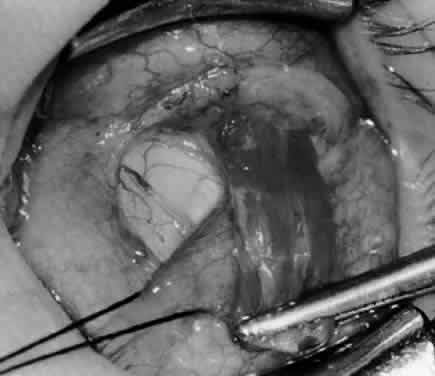

Fig. 1. The standard inferior-temporal fornix incision is made through the conjunctiva and Tenon's capsule with a Westcott scissors. The incision is placed about 8 mm posterior to the limbus, anterior to the fat pad.

Fig. 2. After the lateral rectus muscle is hooked with a Stevens and then a Green muscle hook, the lateral rectus muscle is tented to allow placement of a 4-0 silk suture beneath the insertion of the lateral rectus muscle. The needle tip should glide along the inferior surface of the muscle hook to avoid laceration of the lateral rectus muscle or laceration or penetration of the globe.

Fig. 3. The eye is retracted superonasally with the 4-0 silk traction suture. The suture is attached to the drapes with a hemostat. A Stevens hook is placed along the inferior border of the lateral rectus muscle and drawn temporally. A von Graefe hook is placed within the incision and drawn inferotemporally to expose the inferior oblique muscle.

Fig. 4. A stiff iris repositor can be placed against the sclera to depress the sclera and enhance the view of the inferior oblique muscle. The inferior temporal vortex vein adjacent to the Stevens hook is retracting tissue along the inferior border of the lateral rectus muscle. The second Stevens hook is pointing to the inferior oblique muscle.